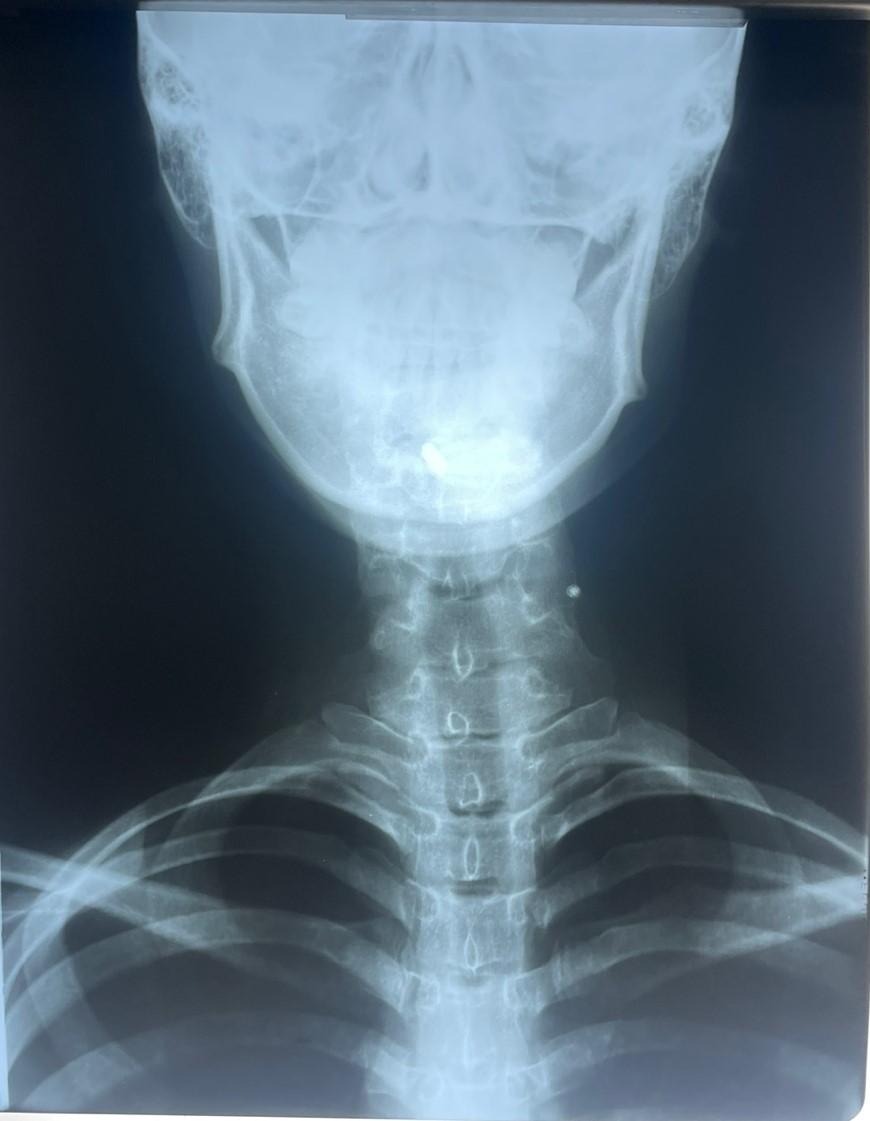

터커리한의원에서 중점 치료를 하는 CBA를 이용한 턱관절 음양자세 교정술은 경추교정에서 끝나는 것이 아니라 CBA스프린트로 교정된 경추 1,2번을 턱관절과 고정을 해준다는 것이 또한 큰 치료의 핵심입니다. CBA스트린 트는 1시간 정도 착용하고 있으면 일자목부터 역커브, 휘어진 목, 좁아진 디스크 간격을 모두 바른 S라인으로 이동, 수술을 시켜줍니다. 경추와 척추 뼈의 문제로 생긴 통증과 이상증을 척추를 직접 물리적인 치료를 하여 몸속에 있는 척추에 정상적인 힘을 가해준다는 것입니다. 그러니 효과가 좋을 수밖에 없고 사경증도 결국엔 휘어있고 역커브가 있는 정도로 인식이 되어서 사경증 치료가 되고 난 후에 다시 X-ray를 찍어보면 목뼈가 바르게 교정된 것을 확인할 수가 있습니다. 사경증은 측만증과 같다고 봅니다. 목이 휘고 등이 휘어있다면 휘어있는 목과 등을 바르게 하는 CBA교정을 터커리한의원에서 지금 받아야 합니다. 치료 기간은 많이 휘어 있으면 오래 걸리고 조금 휘어 있으면 조금 오래 걸립니다. 치료는 제가 해드리지만 기간까지는 알 수 없습니다. 쉽게 생각하고 오시면 안 됩니다. 반드시 오시기 전에는 X-ray 그림을 지참하시고 오시기 바랍니다.https://naver.me/FgiE6Sux